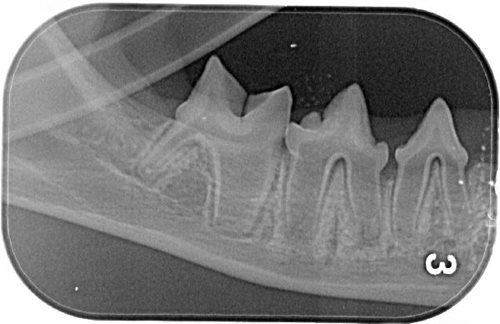

Er zijn ontzettend veel huisdieren die last hebben van hun gebit. Bij dieren ouder dan drie jaar heeft drie van de vier dieren een gebitsprobleem. Dit kan variëren van ontstoken tandvlees en tandplaque tot wortelontstekingen en aantasting van de gebitselementen.

Het is soms moeilijk voor een eigenaar om in te schatten of een dier last heeft van het gebit. Vaak eten de dieren zonder zichtbare problemen en valt er niet veel afwijkends op in het gedrag. Een onaangename geur uit de mond en veel schuren met de snuit zijn uitingen waar eigenaren wel mee naar de dierenarts gaan. Daarnaast wordt bij de jaarlijkse gezondheidscontrole uw dier altijd in de mond gekeken door de dierenarts. De conditie van het gebit zal met u besproken worden en indien nodig maken we een behandelplan.

Vaak begint zo’n behandelplan met het grondig reinigen van het gebit. Dit moet onder narcose gebeuren zodat wij ook onder het tandvlees kunnen reinigen. Als alles schoon is hebben wij goed zicht op alle elementen en checken wij de aansluiting van het tandvlees op de tanden en kiezen. Tegenwoordig hebben we op de kliniek de beschikking over dentale röntgen. Hierdoor kunnen we in een eerder stadium aandoeningen aan het gebit ontdekken en verhelpen. Onze tandheelkundige dierenarts heeft zich toegelegd op dit deelgebied en volgt regelmatig nascholingen. Als het noodzakelijk is kunnen wij ernstig aangetaste elementen direct trekken.

Als alles schoon is en alle elementen geïnspecteerd zijn, polijsten wij het gebit om de ontwikkeling van tandplaque en tandsteen in de toekomst te vertragen.